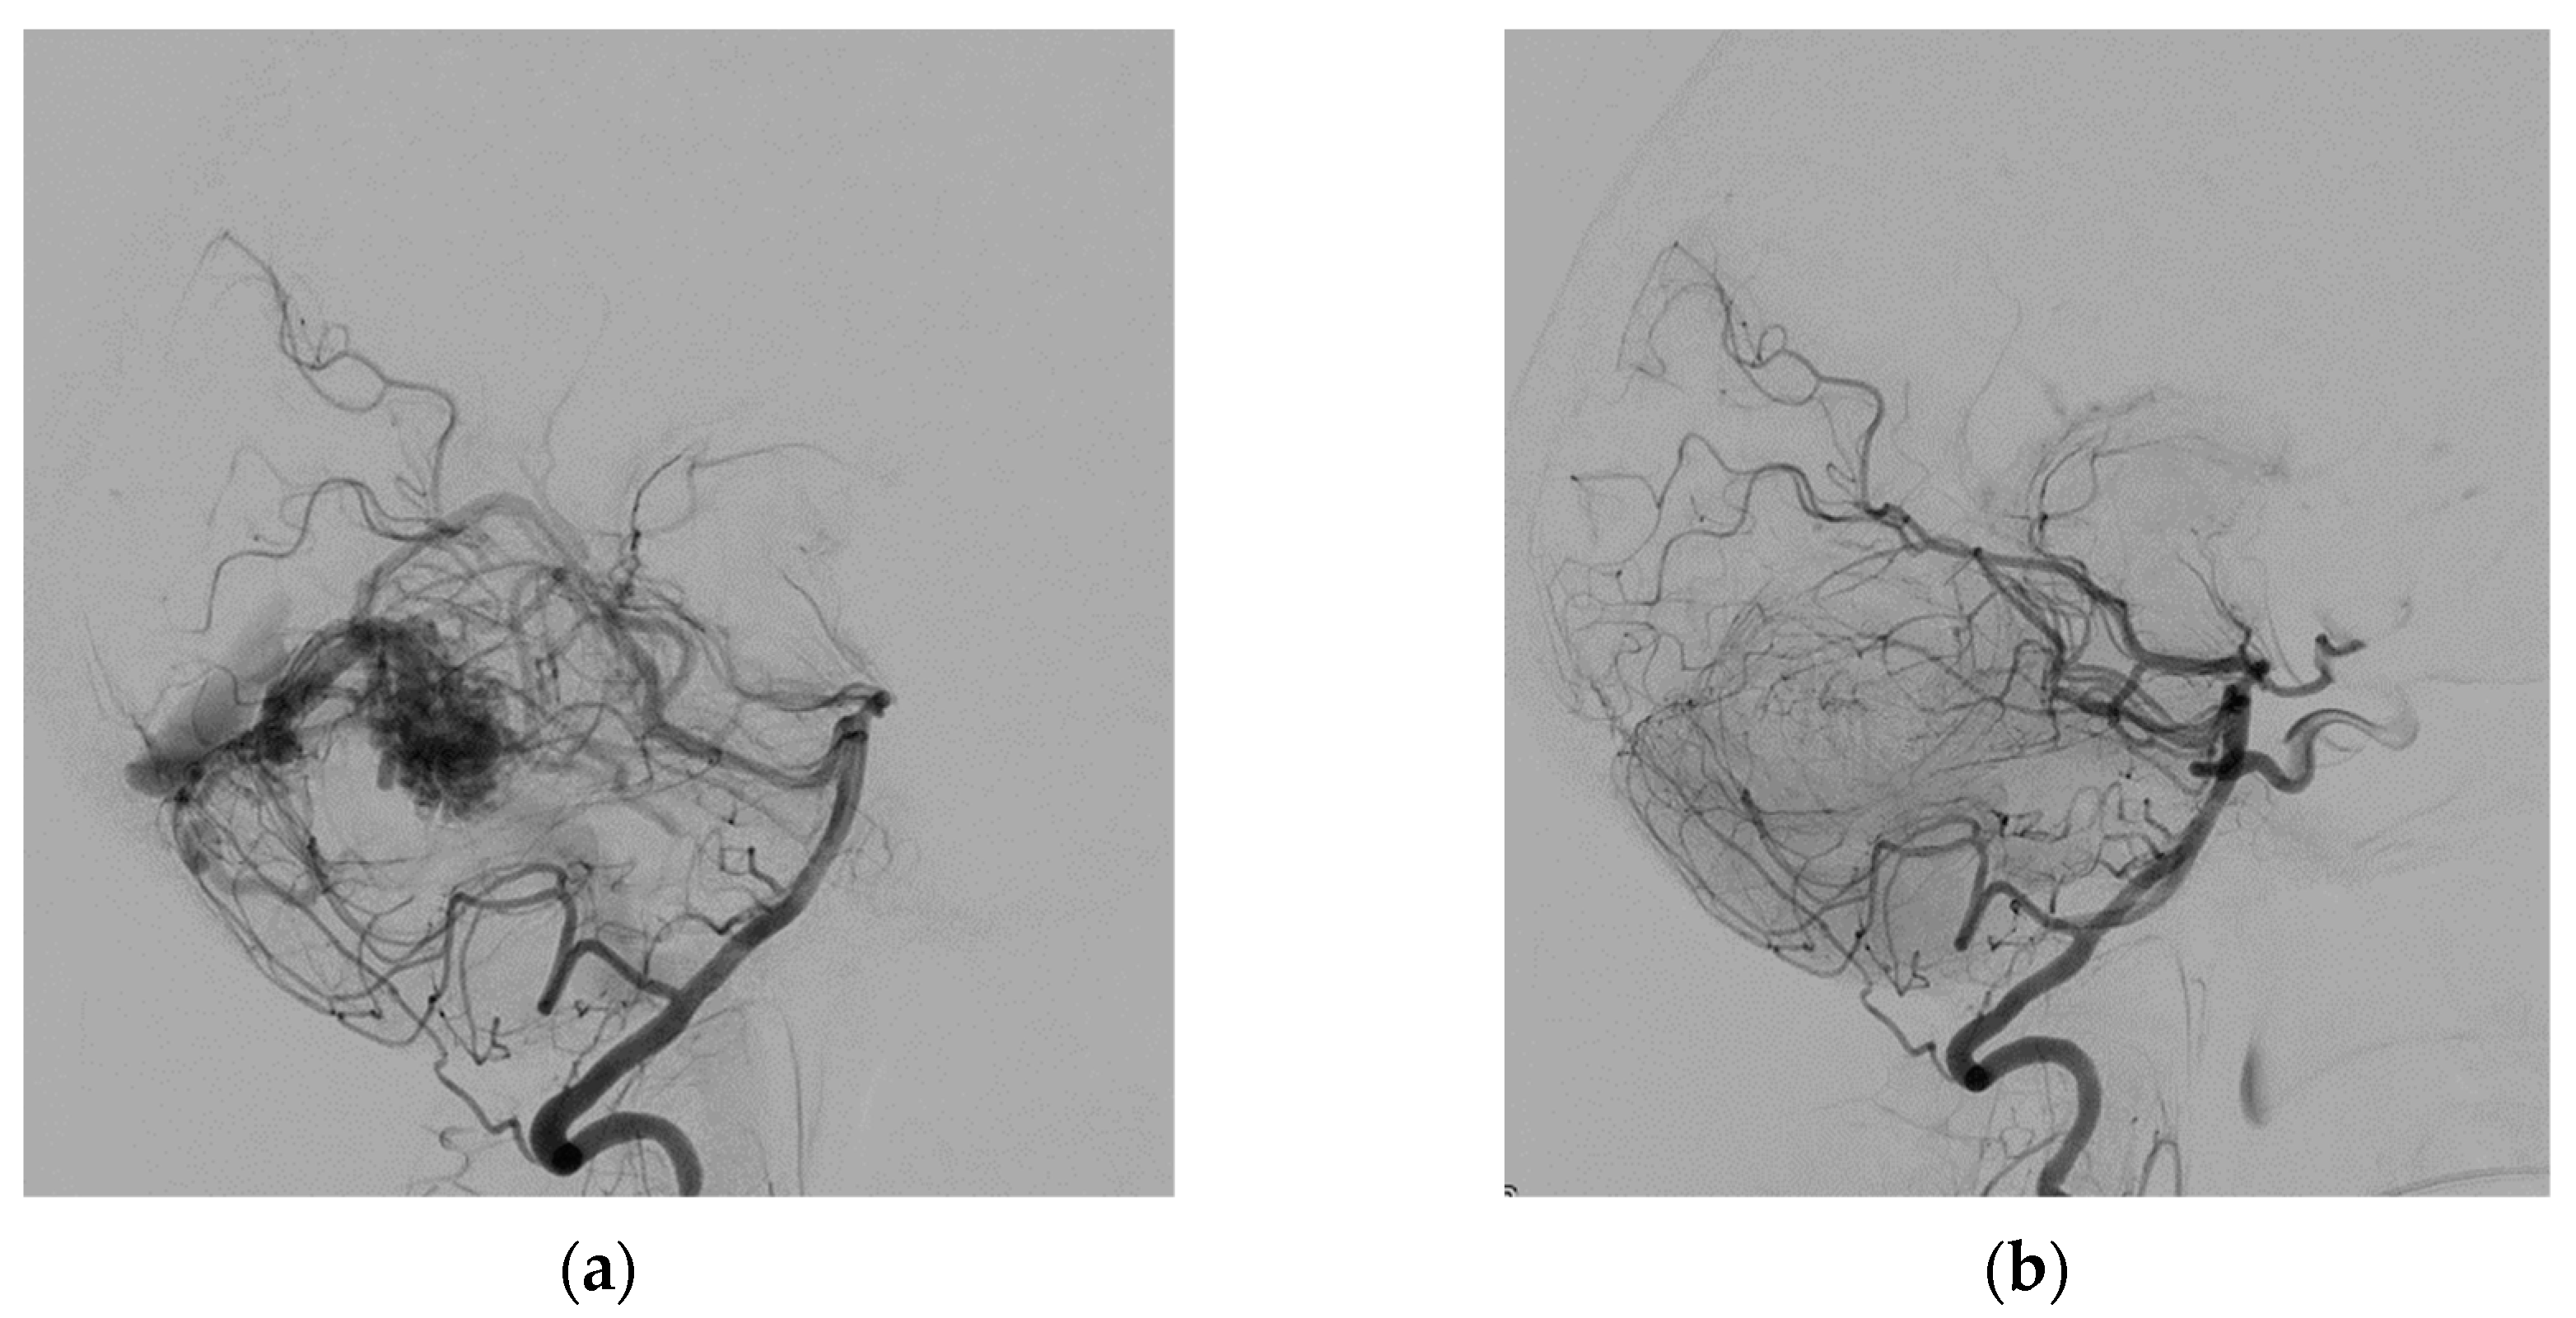

The right common femoral artery was punctured under ultrasound guidance, and a 6F short sheath was placed by the Seldinger technique. The patient was not heparinized. Over the guidewire, the sheath was replaced by a 6F 80 cm long introducer, which was placed in the aortic arch without the use of fluoroscopy. Fluoroscopy was used only in the head and neck area of the patient. The procedure continued by positioning the introducer into the left subclavian artery. Then a 6F guiding catheter was advanced and positioned coaxially into the left vertebral artery. All catheters were flushed continuously with saline solution. The left vertebral artery angiogram confirmed the pial AVM located in the right cerebellum, which was supplied by three branches of the right superior cerebral artery and drain into the straight sinus (Figure 1). Apollo microcatheters (ev3 Neurovascular, Irvine, CA, USA), with a 3 cm long detachable tip length, were navigated into three supplying arteries by guidewires: Hybrid 008.J and Hybrid 007.J (Balt, Montmorency, France), Synchro-10/300 (Stryker Neurovascular, Fremont CA, USA), and Asahi 008/300 (Asahi Intecc, Aichi, Japan). Three feeding arteries were embolized one by one with 25% liquid embolic material PHIL (MicroVention, Tustin, CA, USA) in amounts of 1.55, 0.45, and 1.5 mL. The complete embolization of the AVM was achieved at the end of the procedure (Figure 1). The total procedure time was 1 h and 50 min. The total amount of Visipaque 320 iso-osmolar iodine contrast medium (GE Healthcare, Oslo, Norway) applied to the patient was 54.7 mL.

Figure 1.

Angiogram of the left vertebral artery (lateral view) before (a) and after (b) AVM embolization.